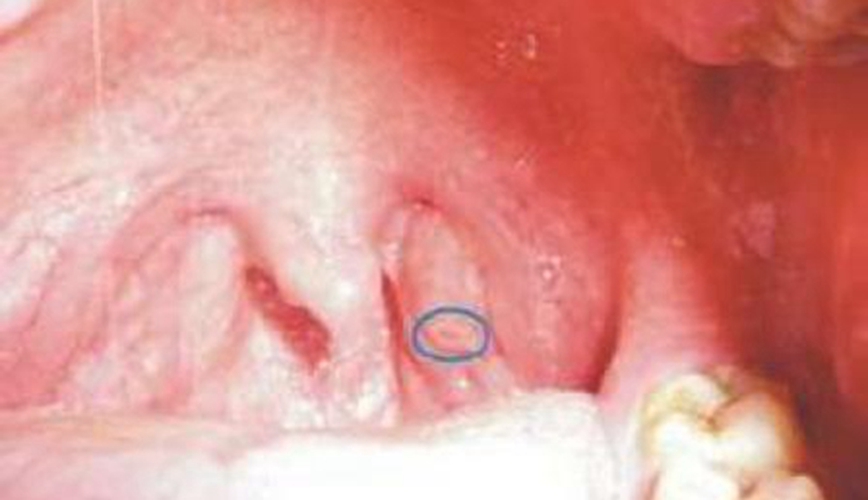

急性咽喉炎圖片

急性咽炎的主要特徵